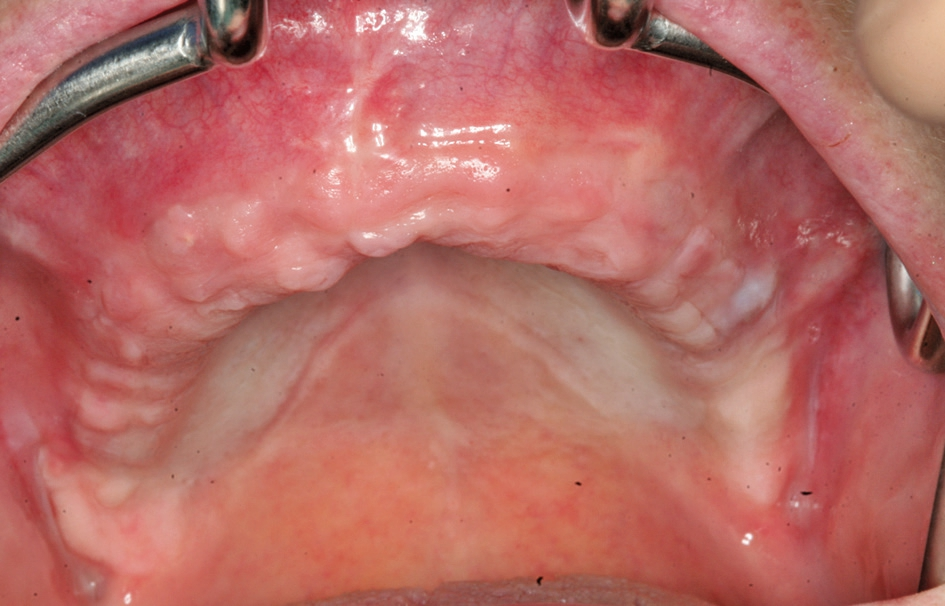

Das Bone Splitting, besonders im Oberkiefer, wird seit vielen Jahren propagiert [13]. Da unterschiedliche Vorgehensweisen vorgeschlagen werden, sind diese in Abhängigkeit des Knochenangebotes, der Anzahl der zu ersetzenden Zähne und der angestrebten prothetischen Versorgung auszuwählen [9, 18] (Abb. 1 und 2).

Die Diskussion erstreckt sich dabei sehr häufig, ob das vestibuläre Knochenangebot deperiostiert oder ob das Bone Splitting im Sinne eines gefäßgestielten Transplantates operiert werden soll [12]. Beim stärker atrophierten Kieferkamm zeigt sich dann die Problematik bei der gefäßgestielten Vorgehensweise häufig darin, dass durch das weite Aufdehnen des Kieferkamms krestal eine relativ breite Fläche entstehen kann, die durch die Auflagerung des Weichgewebes auf dem mobilisierten Kieferanteil nicht zu einem spannungsfreien Wundverschluss führen kann oder bei der Präparation eines Mukosalappens der gedehnte Bereich nicht mit Periost abdeckt wird. Ferner stellt sich die Problematik, dass bei einem zirkulären Vorgehen die Ernährung des Mukosalappens reduziert ist und es somit zu Wundheilungsstörungen kommen kann. Daher empfiehlt sich bei einem ausgedehnten Bone Splitting die Vorgehensweise mit der Präparation eines Mukoperiostlappens, da hier nach einer Periostschlitzung das Weichgewebe ausreichend mobilisiert werden kann, damit eine knöcherne Einheilung unter der geschlossenen Weichgewebsdecke erfolgt.